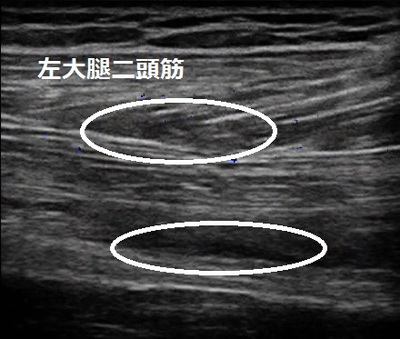

川越市 大学サッカー部所属。 大腿部(もも裏)の痛み、大腿二頭筋、外側広筋肉ばなれ。

当院来院時に足を動かしたところ、左股関節を伸ばす時と膝を曲げる時に鋭い痛みがありました。

膝を伸ばす時にもも後外側の筋肉に痛みがあり、力が入りづらい状態でした。

超音波検査では大腿二頭筋と(画像上部の丸)外側広筋(下部の丸)に肉離れと内出血が認められ

ました。施術では内出血の吸収を促進させる治療を行います。そうすると肉ばなれの箇所の傷口が

ぴったりと癒合して早く治ります。